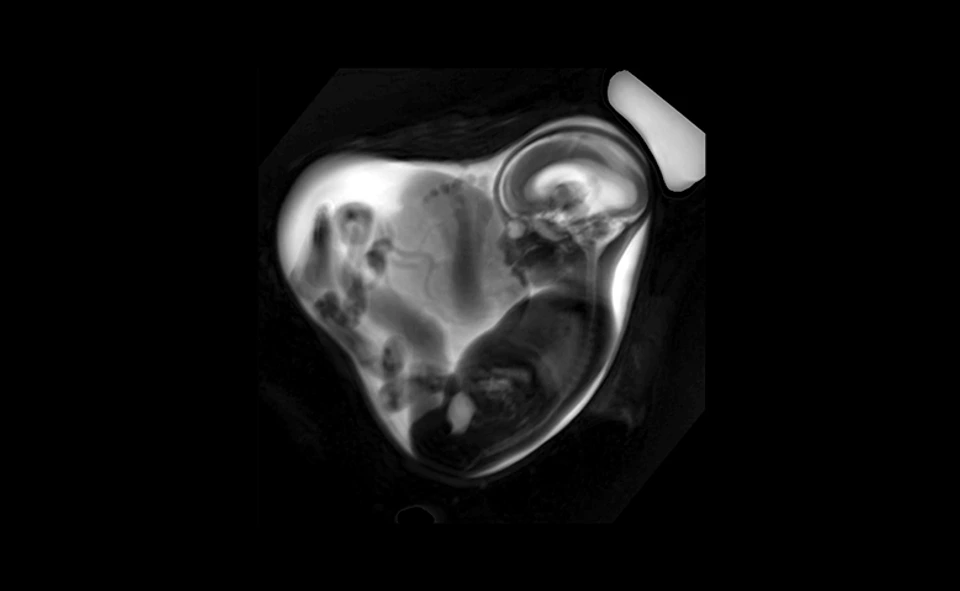

LMU Klinikum Fetale MRT Overview

Schwangerschaft und COVID-19: Reduziertes Lungenvolumen bei Ungeborenen

Ein teilweise deutlich reduziertes Lungenvolumen – das haben Wissenschaftler:innen und Ärzt:innen von Helmholtz Munich und des LMU Klinikums mittels pränataler Magnetresonanz-Tomografie (MRT) bei Feten nachgewiesen, deren Mütter in der…